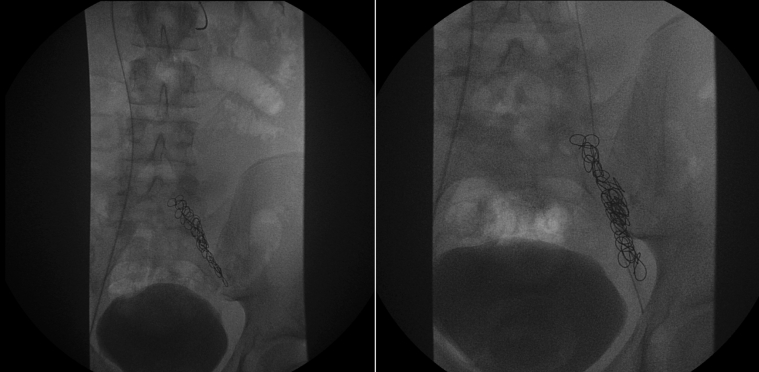

In 2005, at age 15 years, he had a varicocele operation. This was his only past medical history. Reviewing his surgical documentation, this was noted as a difficult procedure. The first attempt was abandoned. He had further radiologic studies to assess feasibility of inserting a microcoil versus a more invasive procedure. It was thought at this point that his anatomy would support a further attempt at coiling the testicular vein. He had approximately 14 microcoils inserted measuring 7 × 70 mm (Figure 1).

Figure 1.

Radiograph

Varicocele procedure.